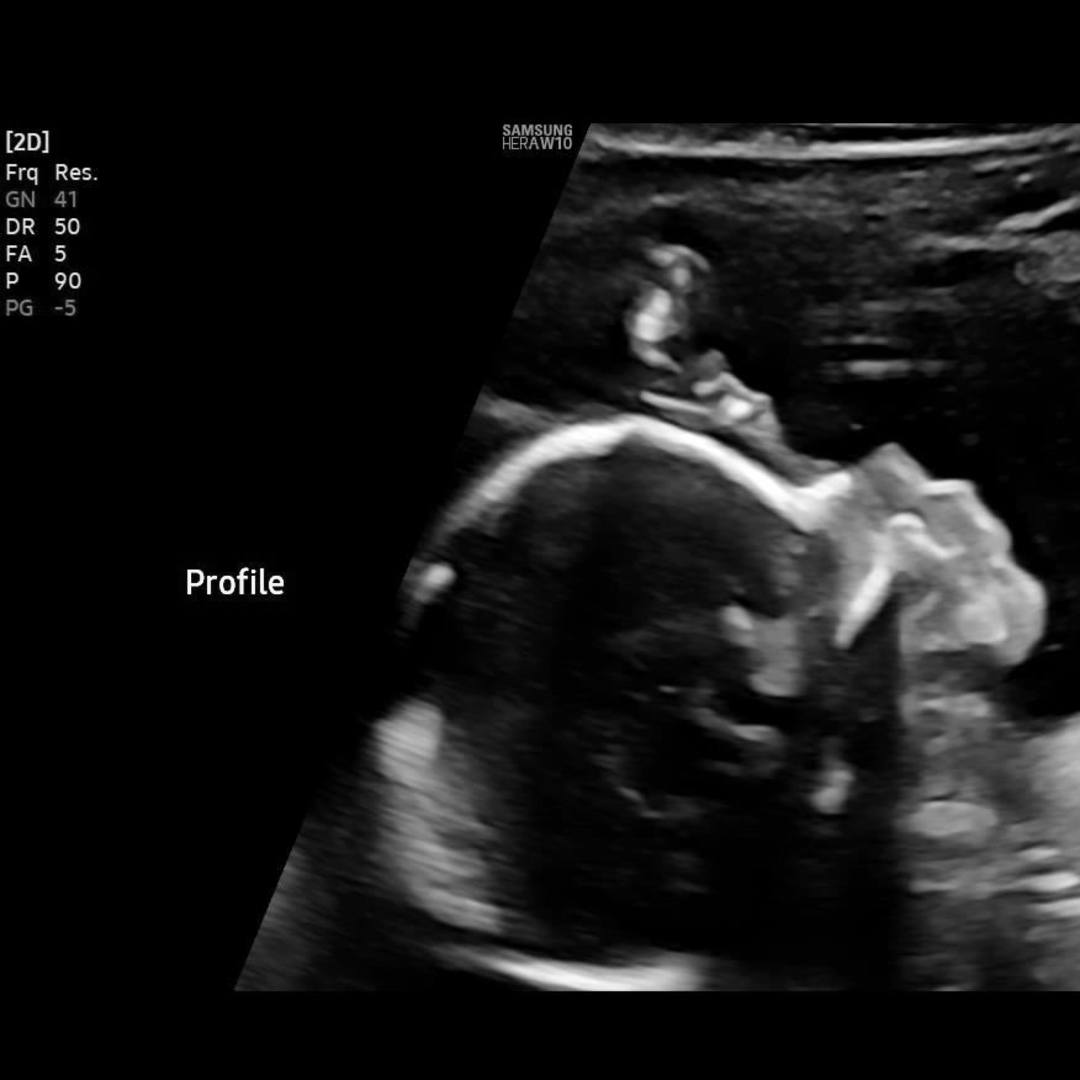

Welcoming Julia & Zach's Baby Girl!

Julia Swanson & Zach Swanson

March 7, 2026